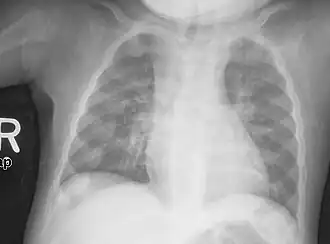

Young children may have bowed legs and thickened ankles and wrists;[19] older children may have knock knees.[16] Spinal curvatures of kyphoscoliosis or lumbar lordosis may be present. The pelvic bones may be deformed. A condition known as rachitic rosary can result from the thickening caused by nodules forming on the costochondral joints. This appears as a visible bump in the middle of each rib in a line on each side of the body. This somewhat resembles a rosary, giving rise to its name. The deformity of a pigeon chest[16] may result in the presence of Harrison's groove.

An X-ray or radiograph of an advanced patient with rickets tends to present in a classic way: the bowed legs (outward curve of long bones of the legs) and a deformed chest. Changes in the skull also occur, causing a distinctive "square-headed" appearance known as "caput quadratum".[20] These deformities persist into adult life if not treated. Long-term consequences include permanent curvatures or disfiguration of the long bones, and a curved back.[21]